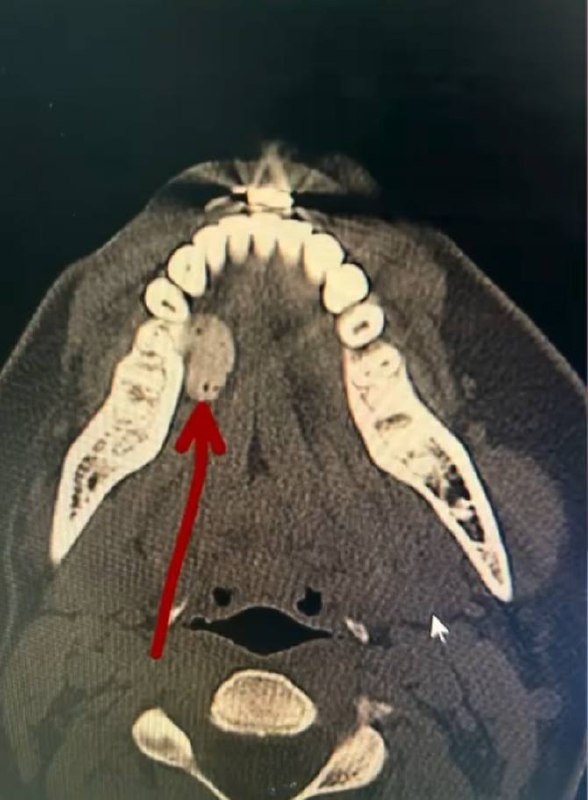

Это компьютерная томография, форма зубов просматривается.

Вопрос: что же такое страшное показано стрелочкой?

Ответ: жвачка! Пациент просто не выплюнул ХубаБубу или Орбит :)